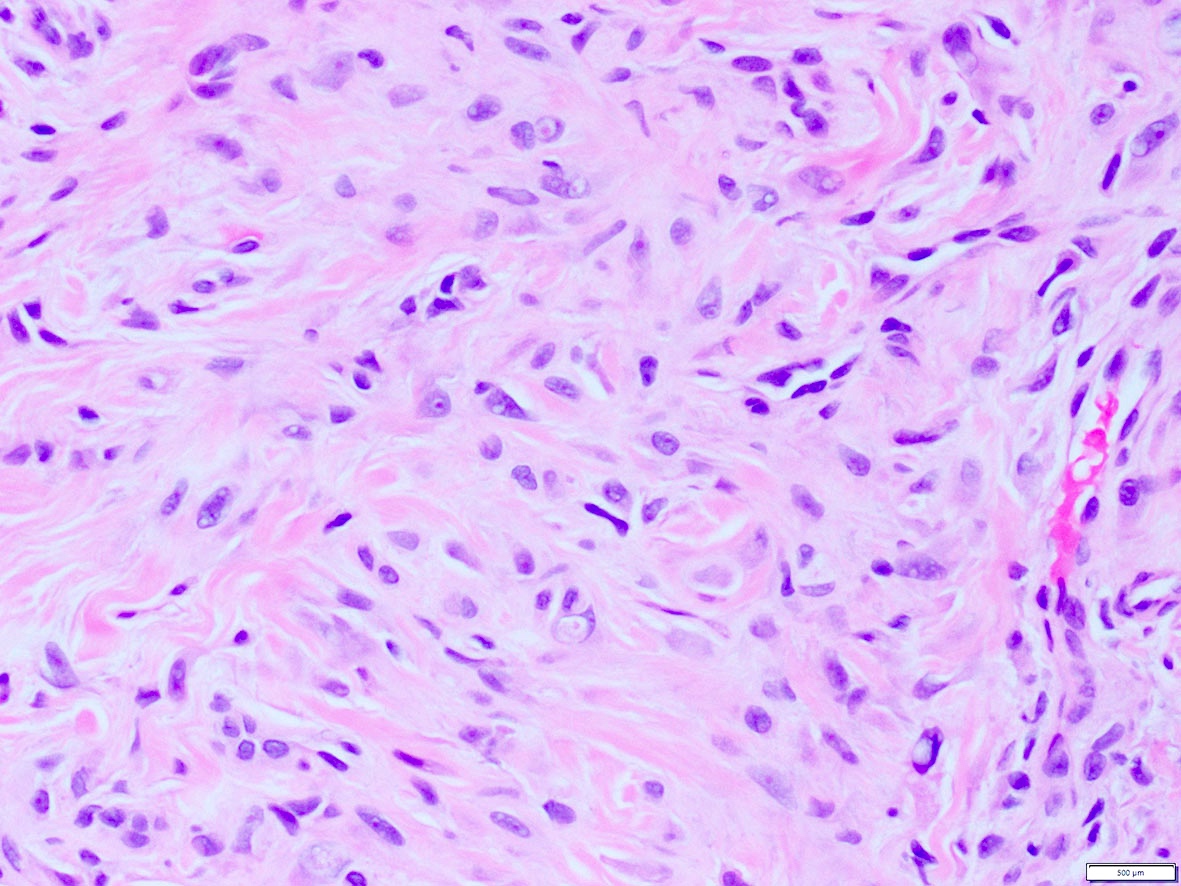

Microscopic (histologic) images

Contributed by A. Cristina Vargas, M.B.B.S., Ph.D., Patricia Guzman, M.D., Fiona Bonar, M.B.B.Ch., Alison Cheah, M.B.B.S. and Martin Jones, M.B.B.S.

Practice question #1

What is the expected diagnosis for a uterine spindle cell tumor with this histological appearance? The tumor displayed focal smooth muscle expression, strong ALK overexpression on IHC and an ALK translocation was confirmed by FISH.

- Endometrial stromal sarcoma

- Epitheliod myofibroblastic sarcoma

- Inflammatory myofibroblastic tumor

- Leiomyoma

- Spindle cell tumor (S100+ / SOX10- / CD34+) with ALK translocations